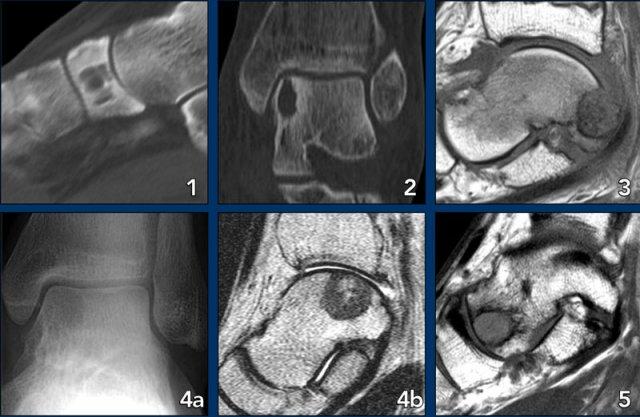

Foot lesions

Here some typical examples of bone tumors in the foot:

- Geode or subchondral cyst in the navicular bone

- Geode or subchondral cyst in the tarsal bone

- Chondroblastoma in the tarsal bone

- X-ray and MRI of a chondroblastoma in the tarsal bone

- Aneurysmal bone cyst in the tarsal bone